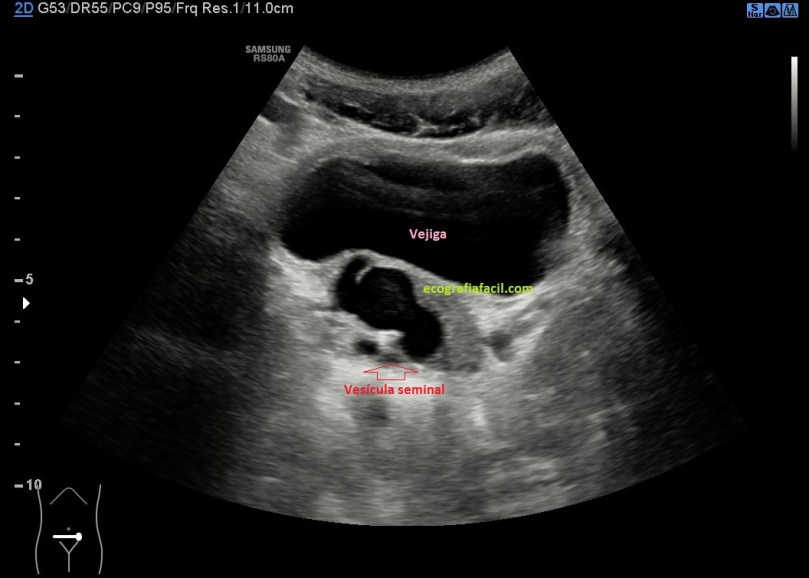

Bajo a la pelvis, a estudiar la vejiga, normal, anecoica, pero observo rápidamente una imagen anecoica, tortuosa, en la parte posterior derecha de la vejiga. Tiene aspecto quístico, con buen refuerzo posterior, bordes lisos, pero tortuosos.

El quiste está en el teórico lugar de la vesícula seminal derecha, su contralateral permanecía normal.

La imagen 4 es de semiología no normal, compara con la imagen 1 y verás como es absolutamente diferente.

Se observa una ecoestructura anecoica, con ligero contenido interno, pero globalmente anecogénica. Bordes lisos y bien definidos, algo tubular.